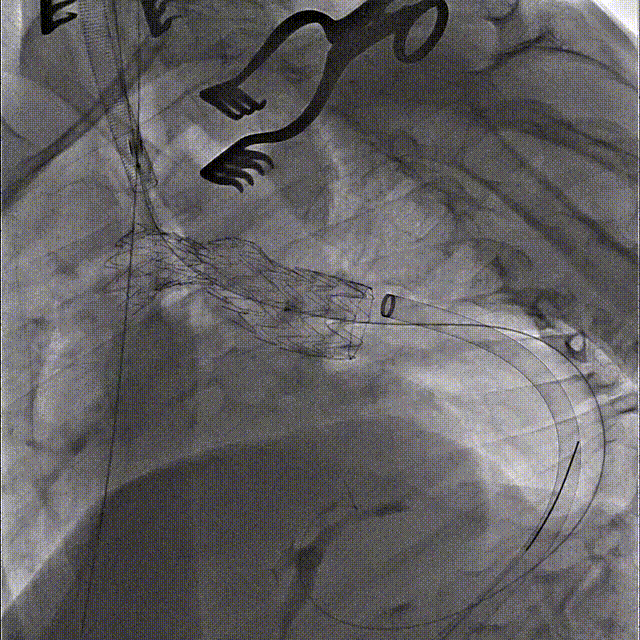

第一步、常规麻醉,消毒铺巾,分离显露左锁骨下动脉、左颈总动脉和左椎动脉备用。经右侧股动脉穿刺植入5F鞘,黄金标记猪尾导管升主动脉造影明确主动脉病变(图2)。

第二步、交换超硬导丝,置入Gore大鞘 DSF2065,顺利通过降主段以及主动脉缩窄处,近端到达无名动脉后缘。

第三步、经鞘内输送Gore TGU262610覆膜支架至无名动脉后缘释放。